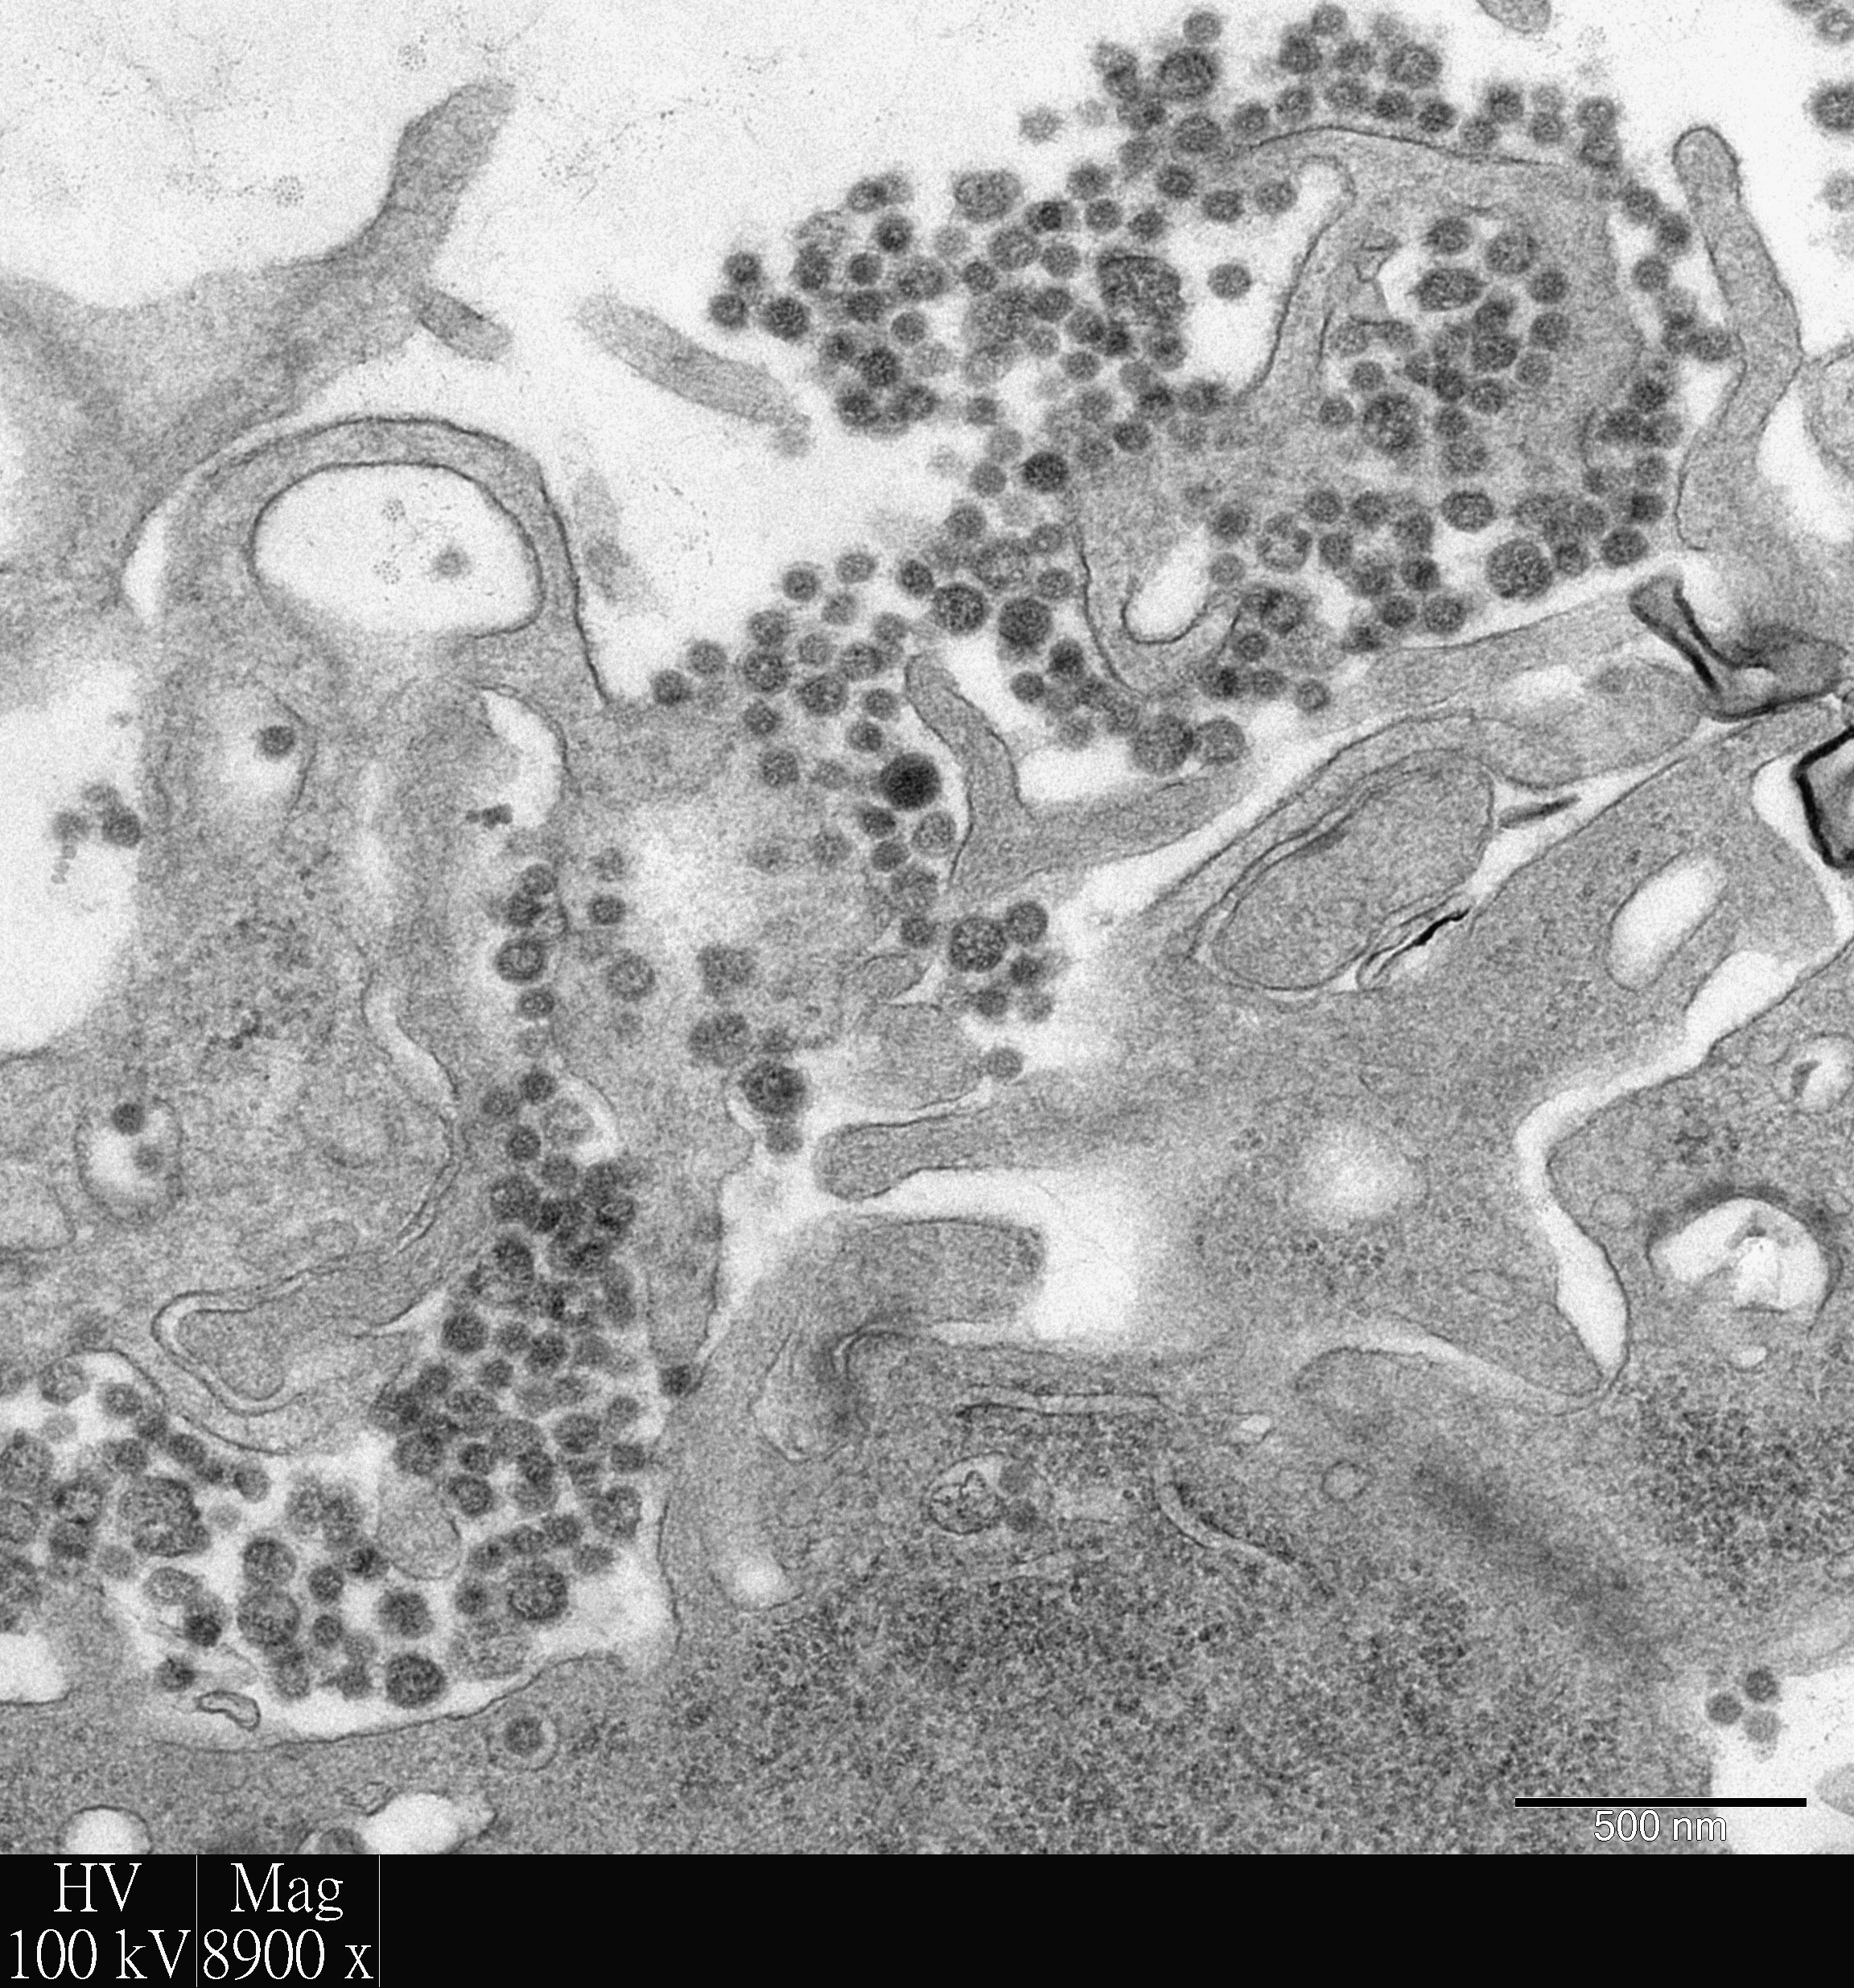

Researchers at the Li Ka Shing Faculty of Medicine of The University of Hong Kong (HKU) used their world-leading human respiratory explant culture system to investigate emerging respiratory viral infections, and in their latest publication focused their attention to improve the treatment of the deadly Middle East Respiratory Virus Syndrome (MERS). It is demonstrated that a combination of two currently licensed agents – interferon and cyclosporine, was able to significantly inhibit virus replication and tissue damage by the MERS coronavirus in human bronchus and lung, when compared to single agent treatment or no treatment. Their findings are now published in Anti-Viral Research, the leading journal of anti-viral treatment (link to the publication).

The explant culture system of the human respiratory tract was developed by Professor John Nicholls of HKU Department of Pathology, in conjunction with Dr Michael Chan, Dr Renee Chan, Professor Leo Poon and Professor Malik Peiris at the School of Public Health, in 2005, in order to develop a laboratory based method for studying severe respiratory virus infections with a more faithful replication of disease mechanisms and treatment outcomes in humans. The system is proved to be more effective for the study than alternative experimental methods, such as cell lines grown in culture or experimental animals, as the latter often fail to reproduce the situation in human respiratory tract.

The explant culture system uses respiratory tissues removed from patients undergoing surgery at Queen Mary Hospital, which are normally discarded but are now reserved with ethical approval for the purpose of research. After over eight months of optimization of the study, this system is now accepted by the World Health Organization (WHO) as a model for pandemic risk assessment of animal influenza virus infections, and has also been utilized by biotechnology companies to evaluate potential antiviral compounds. Funding from the Food and Health Bureau, HKSAG and The Research Grants Council, University Grants Committee, has enabled the system to be developed, optimized and maintained.